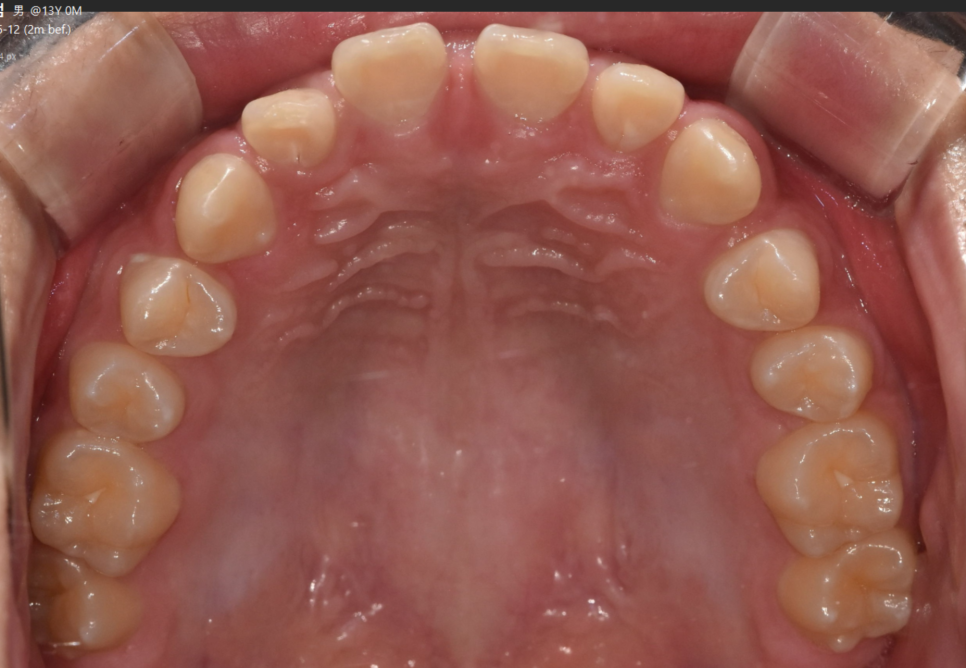

가운데 치아가 눈에 띄게 벌어져있는 환자분

앞니끼리 벌어진 공간이 좁을 경우는

레진이라던가

라미네이트, 크라운과 같은 보철로도 메울 수가 있습니다.

대신 메운 공간만큼 치아 사이즈가 커지는 단점이 있겠죠.